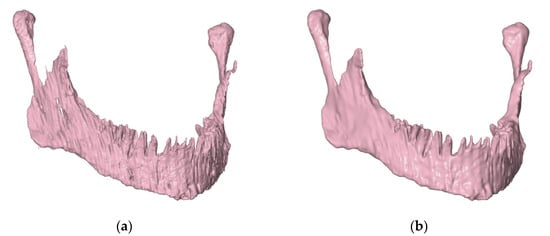

- Creation of an accurate model of the mandible together with the temporomandibular joint. The main assumption was to create a model that could be used for numerical analyses of various clinical cases, allowing the simulation of the work of fixing elements, assessment of the strength and durability of the fixation, and at the same time, without unnecessary simplifications, reflect real human anatomy. The input data were DICOM images obtained from medical imaging using computed tomography. Obtaining three-dimensional models of individual anatomical structures required the segmentation of tomographic images and then edition of the generated surface objects. Reverse engineering software for free modeling and a CAD program for parametric modeling were used.

2.3. Edition of STL Models

2.4. Preparation of a Solid CAD Model

3.1. CAD Model